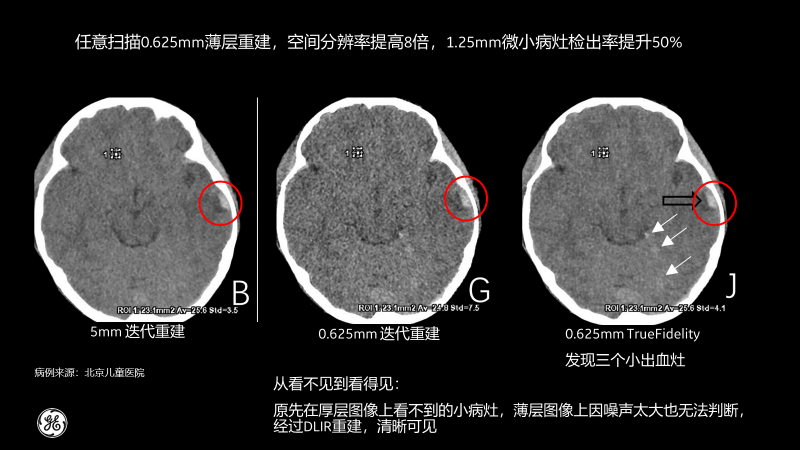

相比傳統CT圖像對腹部檢查一般都選擇5mm厚層重建,TrueFidelity可對任意體型任意部位的檢查進行0.625mm的薄層圖像重建,真實還原圖像的解剖細節和紋理,提高微小病灶的發現幾率,有助于早診早治,極大提高醫生的診斷信心。

尤其是對于天然對比度低的組織結構,比如腹部成像,TrueFidelity的診斷優勢尤為明顯,并為臨床診斷帶來了顯著突破。

北京兒童醫院的測試病例也顯示,經過TrueFidelity,任意掃描0.625mm薄層重建,空間分辨率能提高8倍,1.25mm微小病灶檢出率提升50%,最終額外發現了3個之前看不到的微小病灶。